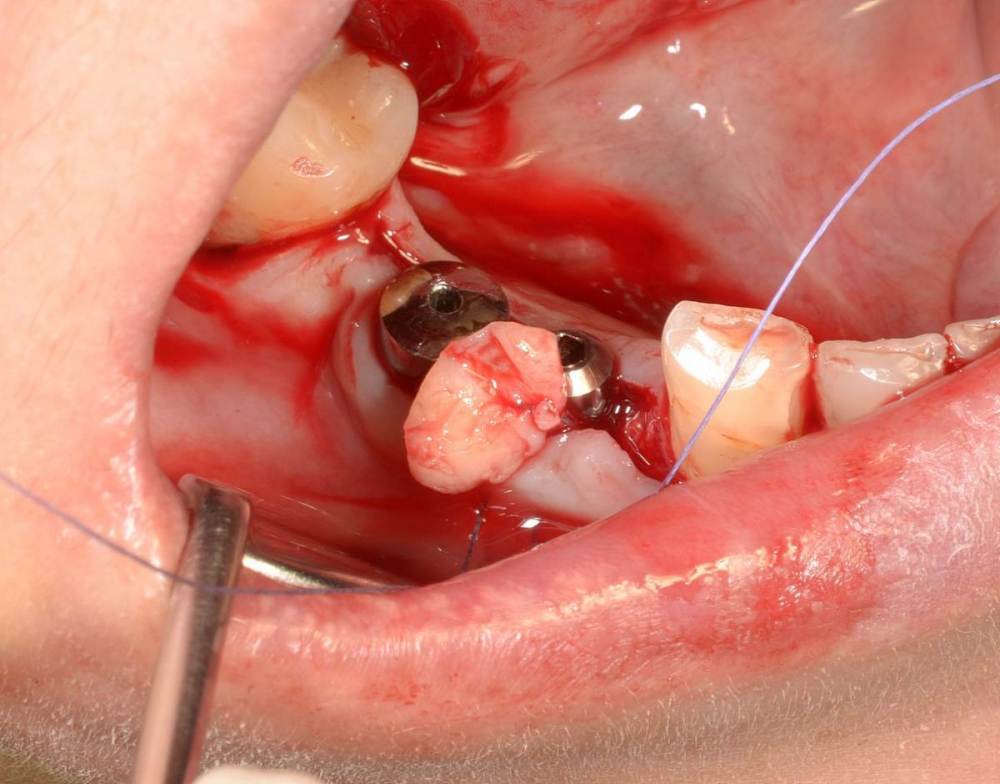

Большой Зеленый Опубликовано 27 мая, 2022 Поделиться Опубликовано 27 мая, 2022 Аналогично..) 4 1 Ссылка на комментарий

Большой Зеленый Опубликовано 27 мая, 2022 Поделиться Опубликовано 27 мая, 2022 Через 9 лет. Есть немного рецессии.. 2 Ссылка на комментарий

Большой Зеленый Опубликовано 27 мая, 2022 Поделиться Опубликовано 27 мая, 2022 4 часа назад, pit сказал: Это связано исключительно с вестибулярной позицией импланта. Это как раз к вопросу про те минимальные 2мм до вестиболярной стенки, вне зависимости есть она или ты ее создаешь. С тех пор я стал хитрее умнее и опытнее ))) 1 час назад, alboard сказал: А в чем смысл ее сохранности, если препарируя под имплантат вы все равно ее в большинстве случаев сносите? Первичная стабильность импланта зачастую достигается только перегородкой.. Ссылка на комментарий

Женька Опубликовано 27 мая, 2022 Поделиться Опубликовано 27 мая, 2022 @Большой Зеленый это вроде ваш старый кейс? напомните пожалуйста, тут присыпка+мембранинг вестибулярно и вестибулярным лоскутом слегка послабленным всё закрыли? Ссылка на комментарий

Большой Зеленый Опубликовано 28 мая, 2022 Поделиться Опубликовано 28 мая, 2022 12 часов назад, Женька сказал: @Большой Зеленый это вроде ваш старый кейс? напомните пожалуйста, тут присыпка+мембранинг вестибулярно и вестибулярным лоскутом слегка послабленным всё закрыли? Да все так и есть как Вы и описали. Работе почти 10 лет. Присыпка мп3 от остеобила сверху "ильгамовская" губка . Считаю что результат вполне удовлетворительный. Рецессия обусловлена как уже сказали выше вестибулярным положением импланта ,ну и недозаглублен чуток. Ссылка на комментарий